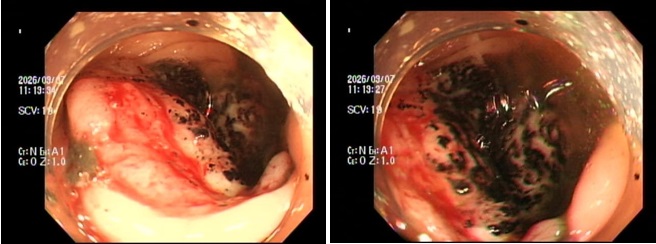

Trường hợp đầu tiên là P.V.P.U (sinh năm 1991) đến khám chỉ vì... ông xã thấy dạo này da dẻ quá xanh xao. Bản thân U thỉnh thoảng cũng cảm thấy đau bụng nhẹ, thoáng qua nhưng lại tặc lưỡi bỏ qua vì nghĩ là rối loạn tiêu hóa thông thường. Khi thăm khám, bác sĩ phát hiện chị bị thiếu máu nặng. Ngay lập tức, chị được chỉ định nội soi đại tràng, kết quả khiến cả hai vợ chồng sững sờ: Có một khối u lớn ở đại tràng phải, bề mặt loét và rất dễ chảy máu, kết quả mô học khẳng định: Ung thư đại trực tràng.

Trường hợp thứ 2 là anh N.H.H.H (sinh năm 1995) đến viện với dáng vẻ mệt mỏi rã rời, than phiền hay bị chóng mặt kèm theo rối loạn đi cầu. Cứ nghĩ do làm việc quá sức, nhưng kết quả xét nghiệm lại báo động tình trạng thiếu máu nặng. Bác sĩ cho tiến hành nội soi đại trực tràng và phát hiện một khối u dạng vòng nhẫn đang chảy máu rỉ rả ở vùng trực tràng. Giải phẫu bệnh một lần nữa gọi tên: Ung thư trực tràng.

Khi làm xét nghiệm máu cho các bệnh nhân trẻ này, bác sĩ thường thấy biểu hiện thiếu máu hồng cầu nhỏ, nhược sắc (thường do thiếu sắt). Sắt là nguyên liệu tạo nên hồng cầu để mang oxy đi nuôi cơ thể. Khi thiếu sắt, cơ thể không đủ oxy hoạt động, dẫn đến hệ quả tất yếu là chóng mặt, mệt mỏi, hụt hơi và da xanh xao. Vậy lượng sắt và máu của những người trẻ này đã biến đi đâu? Câu trả lời nằm ở các khối u trong đường tiêu hóa. Khối u đại tràng (đặc biệt là đại tràng phải) thường không gây tắc ruột ngay mà có bề mặt dễ viêm loét. Chúng tựa như những "kẻ cắp", mỗi ngày làm chảy một lượng máu rất nhỏ lẫn vào phân mà mắt thường khó nhận ra (máu ẩn trong phân). Tình trạng mất máu rỉ rả kéo dài qua nhiều tháng đã vắt kiệt lượng sắt dự trữ, gây thiếu máu nặng. Đến khi cơ thể kiệt sức báo động, bệnh nhân đi khám thì khối u thường đã lớn, xâm lấn hoặc di căn.